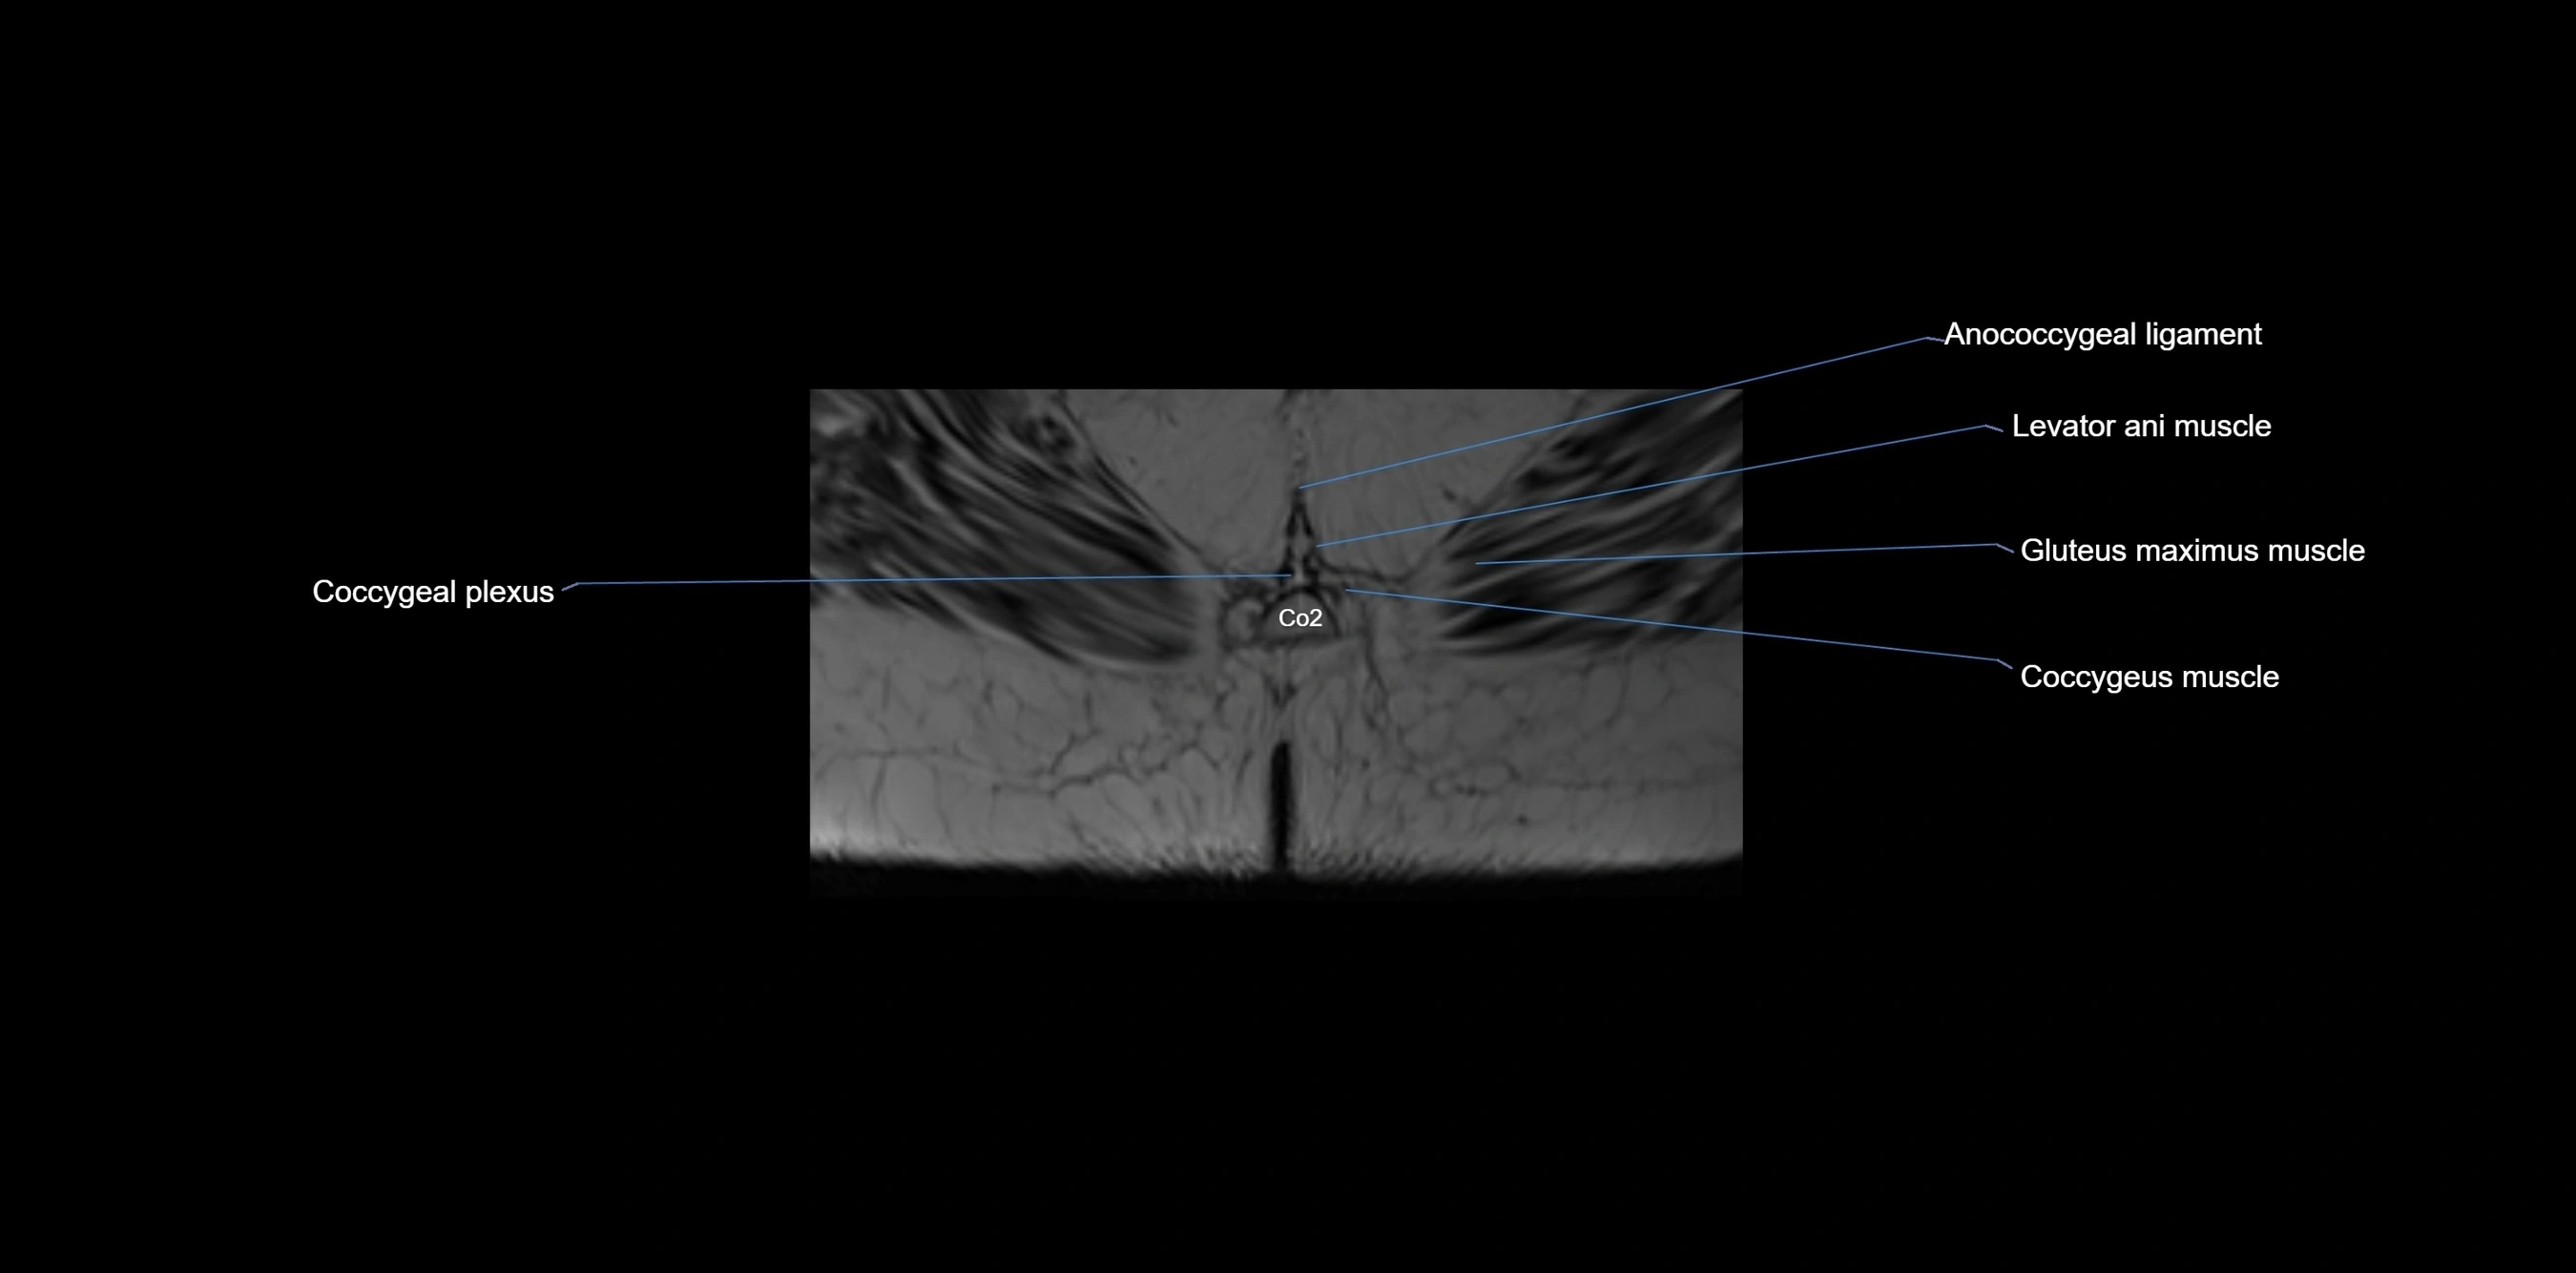

MRI image

image